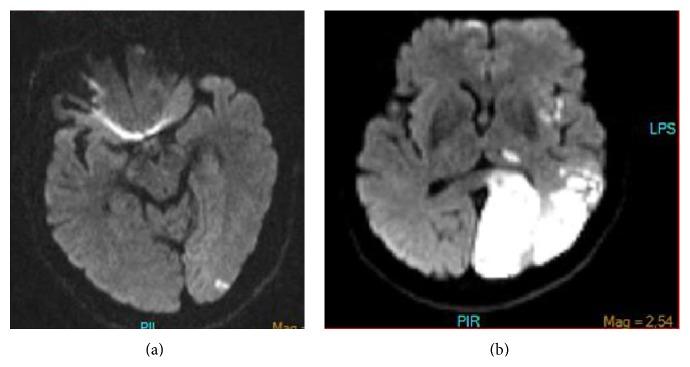

Fetal type PCA may positively affect clinical outcome in patients with ischemic stroke such as protection of a reserve blood flow capacity as well as negative effect on clinical outcome such as certain atypical pathological manifestations. We presented a patient with a posterior cerebral artery territory infarction due to an unexpected etiology as stenosis of internal carotid artery (ICA) with existence of fetal type PCA.

胎儿型大脑后动脉(PCA)可能对缺血性中风患者的临床结局产生积极影响,如保护储备血流能力,也可能产生消极影响,如某些非典型病理表现。我们报告了一名因意外病因——颈内动脉(ICA)狭窄且存在胎儿型PCA——导致大脑后动脉供血区梗死的患者。